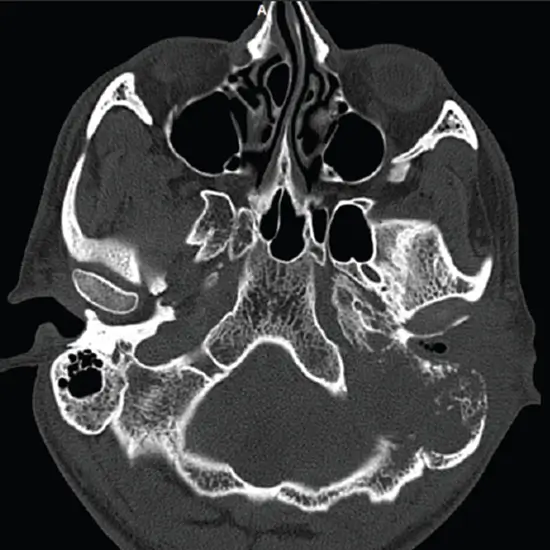

The mastoid is a part of the skull located behind the ear. It is made up of air sacs and looks like a sponge. NCCT Both Mastoid is Non-Contrast Computed Tomography of both Mastoid is an imaging scan that is used to diagnose the bone ridge behind the ear. The images obtained from the scan evaluate the structures of the ear and its surrounding tissues.

Doctors recommend NCCT for both Mastoid to diagnose mastoiditis that an infection of the air spaces of the mastoid, an Ear infection, or an abnormal skin growth in the middle ear behind the eardrum. It is also used if the doctor suspects there is an injury or fracture of the mastoid bones or abnormal growth in the mastoid bone region.